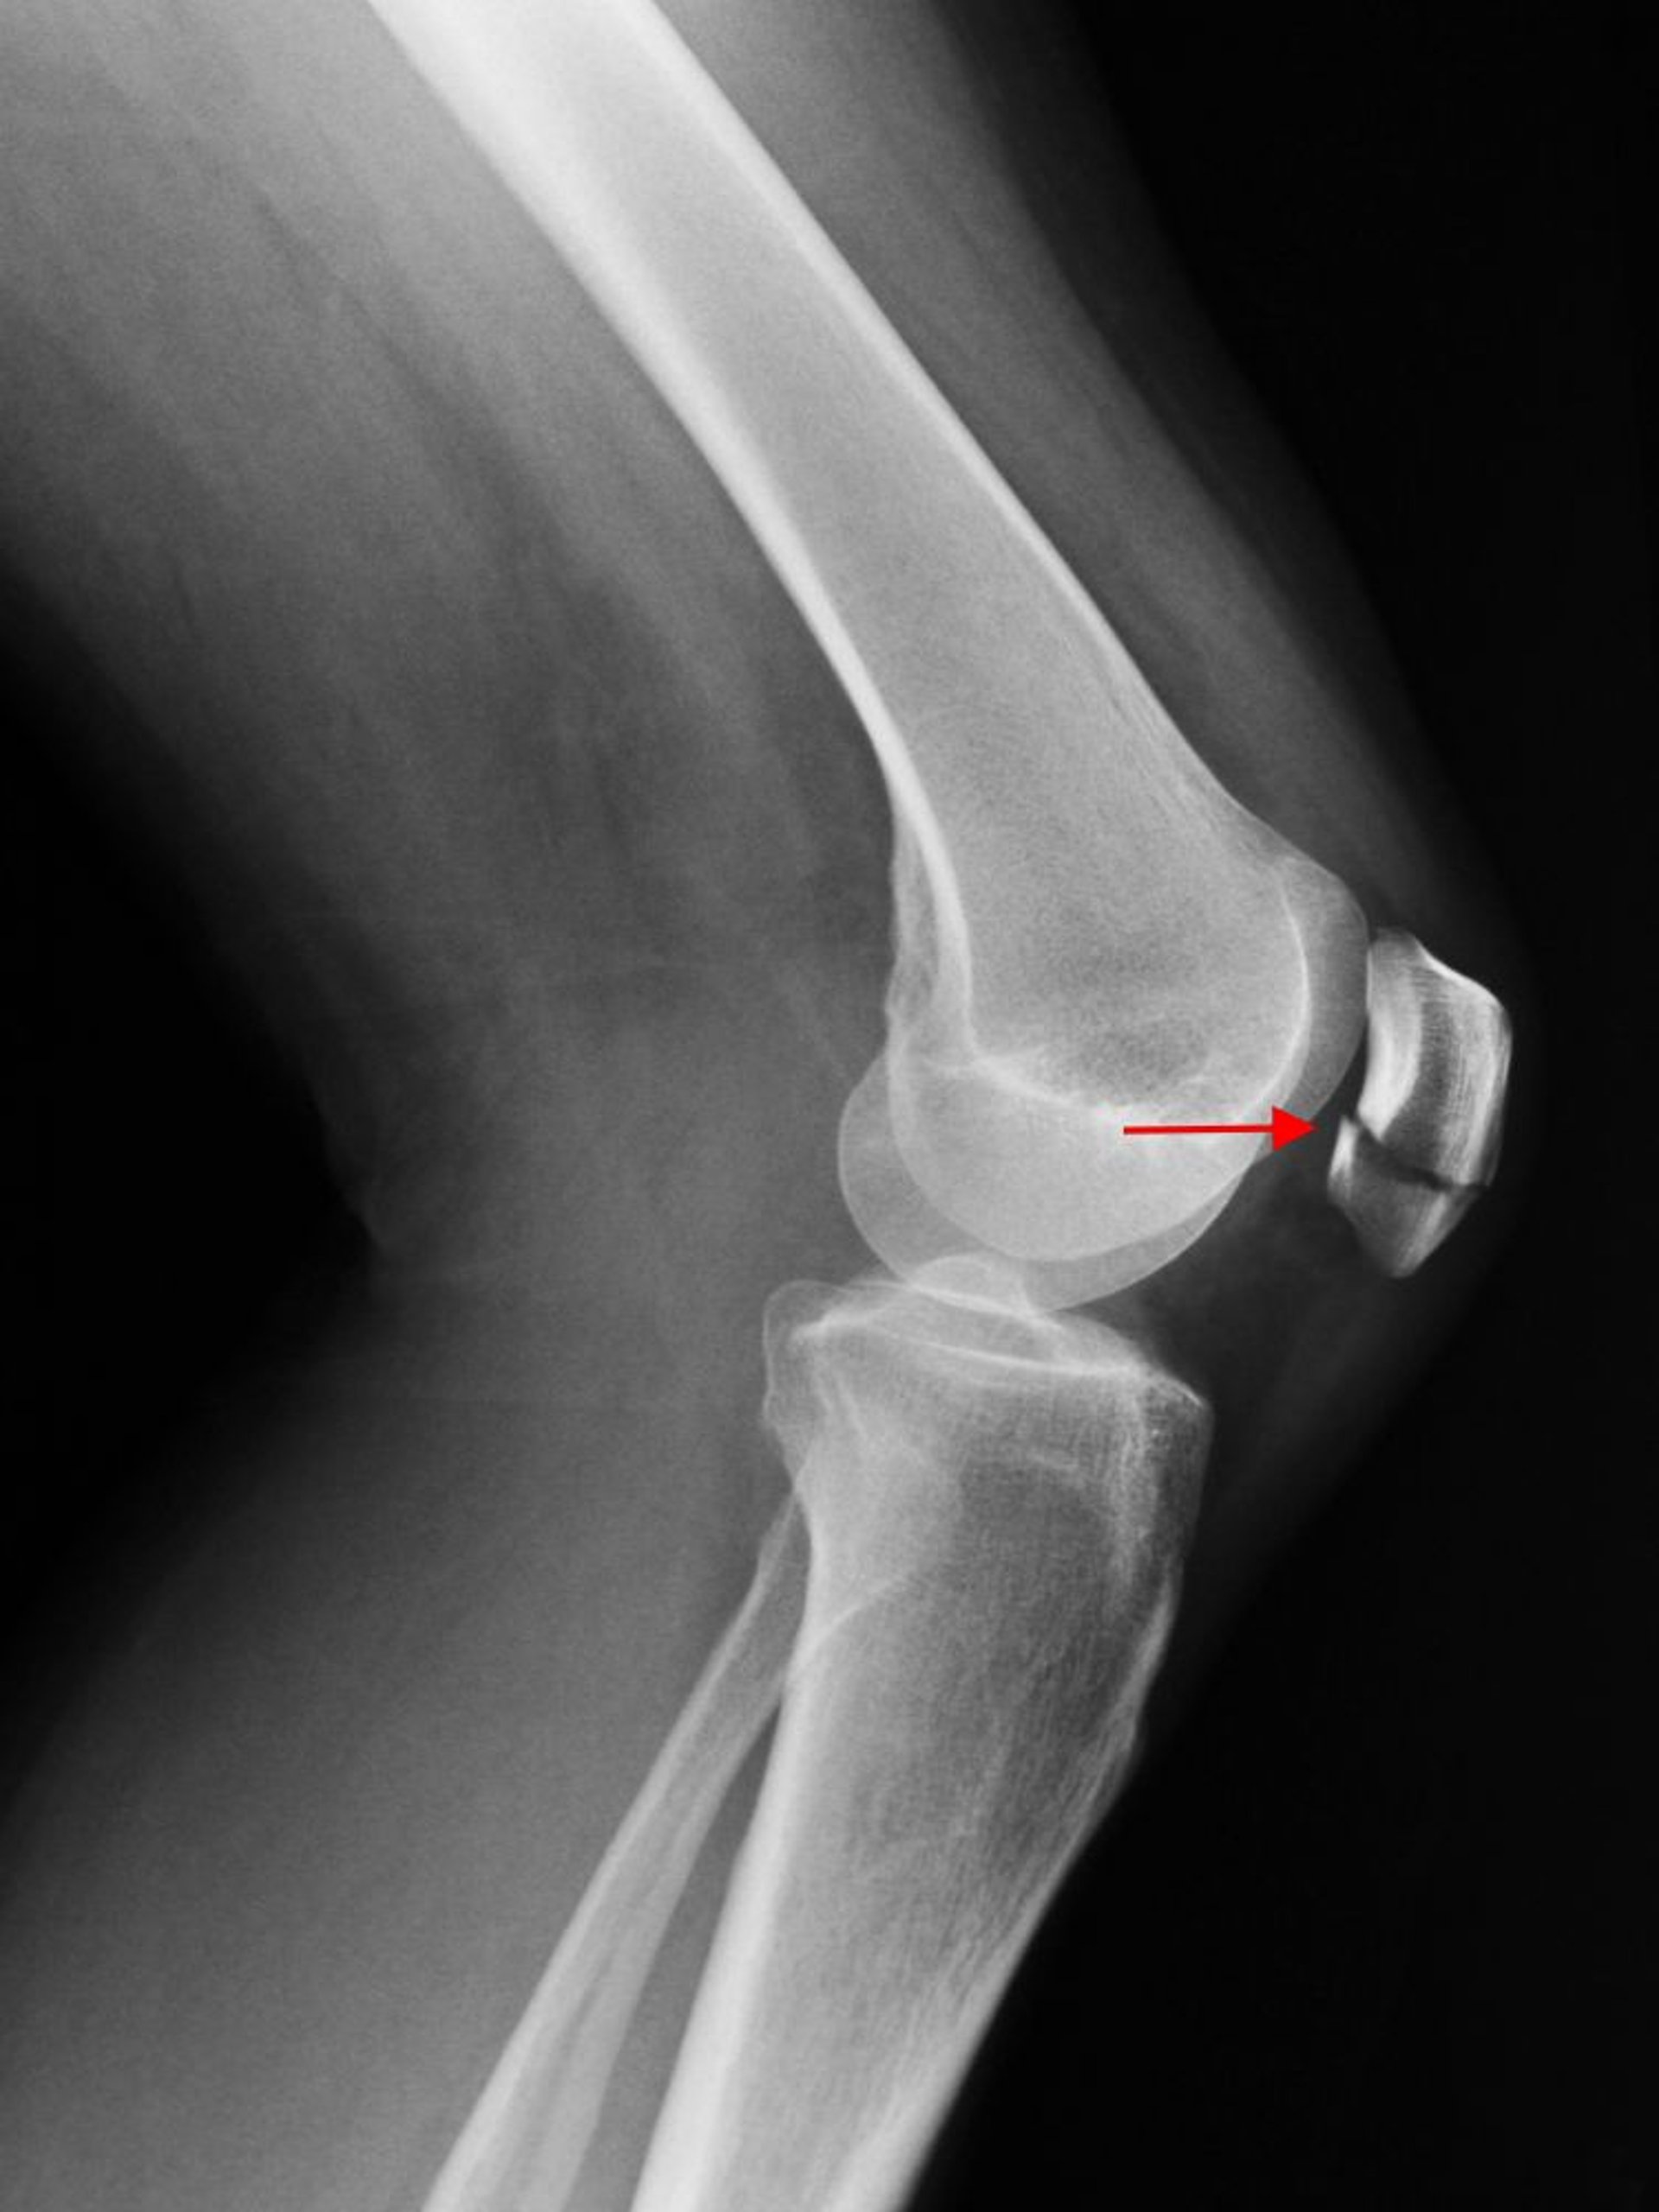

Перелом надколенника

Рентген коленного сустава в боковой проекции показывает поперечный перелом надколенника (стрелка).